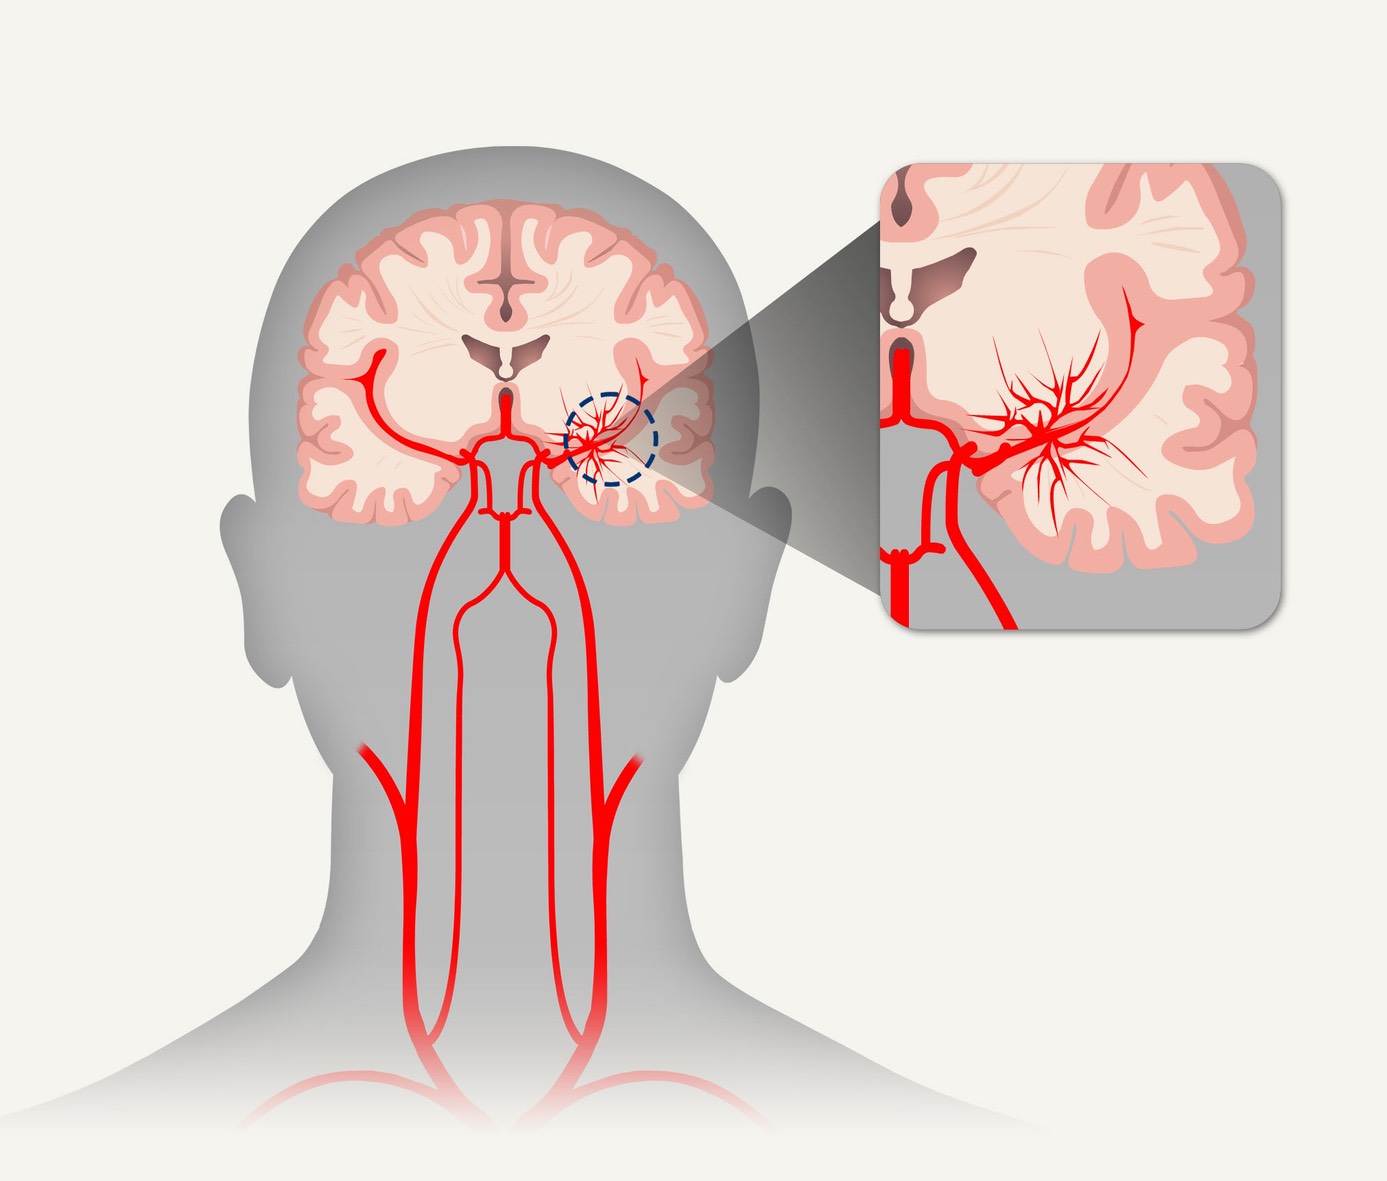

모야모야병은 뇌혈관, 특히 뇌로 혈액을 공급하는 내경동맥과 그 주변 주요 혈관이 점점 좁아지고 막히는 희귀 난치성 질환으로, 혈류가 줄어든 뇌는 부족한 혈액을 보충하기 위해 가느다란 미세측부혈관들을 새로 만들어냅니다. 이 작은 혈관들이 연기처럼 보인다고 하여 일본어로 ‘모야모야(안개·연기)’라는 이름이 붙었습니다. 소아부터 성인까지 폭넓게 나타나며, 특히 5~10세 어린이와 30대 전후의 여성에서 비교적 많이 발견되는 경향이 있습니다. 증상은 일시적 마비, 언어장애, 두통, 실신, 경련 등 매우 다양해 뇌졸중과 유사하거나 초기에는 가벼운 신경학적 증상으로만 나타나 진단이 늦어지기도 했습니다. 질환이 진행하면 허혈성 뇌졸중(뇌경색)이나 출혈성 뇌졸중 위험이 증가하여 반드시 전문적인 관리가 필요합니다. 아직 완전히 예방할 수 있는 방법은 없지만 조기 진단과 적절한 치료를 통해 뇌 기능을 보호하고 삶의 질을 유지할 수 있습니다.

모야모야병은 뇌기저부의 주요 혈관이 서서히 협착되고 막히면서 뇌혈류가 감소하는 만성 진행성 뇌혈관 질환입니다. 협착이 진행된 부위를 대신해 뇌는 생존을 위해 얇고 약한 혈관망을 만들어 혈류를 보충하려 하고, 이 새로운 혈관들이 촬영 영상에서 연기처럼 퍼져 보인다고 하여 ‘모야모야’라는 이름이 붙었습니다. 기전적으로는 내경동맥 말단부와 중대뇌동맥·전대뇌동맥의 기시부에 병변이 가장 잘 생기며, 시간이 지남에 따라 양쪽에 대칭적으로 나타나는 특징을 보였습니다. 이 질환은 단순한 혈관 협착이 아니라 진행성 변화이기 때문에 치료하지 않으면 혈류 부족이 심해지고 뇌 손상이 누적될 수 있습니다. 또한 뇌기능이 체력·호흡·체온 변화 등에 민감하게 반응하기 때문에 과호흡, 울음, 격렬한 운동, 감염 등으로 증상이 악화될 수 있습니다. 즉, 모야모야병은 시간이 지나면서 뇌혈류를 감소시키고 뇌졸중 위험을 높이는 질환이며, 평생 관리가 필요한 만성적 특성을 갖고 있습니다.